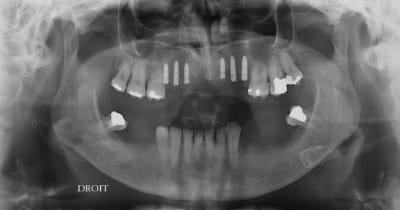

Très joli le résultat de la greffe

PS il te manque 1 ou 2 implants en position 11-21...

J'aime pas le long espace antérieur...ou c'est la photo qui donne cette idée...

11 21 pas favorable en même temps que 12/21

si il faut je mettrais ça après mais 6 implant pour 8 dents ça doit le faire, j'ai respecter la position par rapport à son partiel

pano ?

pas avant la semaine prochaine, je n'ai fait que des rétros.

6 implants, 8 dents, ça va le faire !!